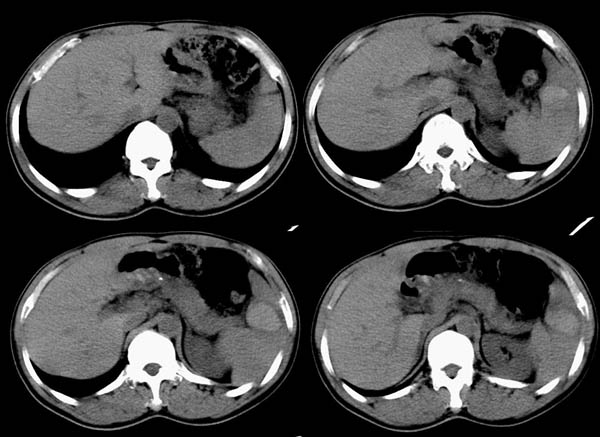

m50y以腹疼、腹胀2小时就诊。腹透肠胀气较明显,余无明显异常。做ct时腹疼已明显缓解;病人否认外伤史,否认血液病变、否认肝炎史。建议第二天做ct增强,病人第二天放弃了增强。脾脏区较高密度影ct值为60hu,正常脾脏ct值为45hu(窗宽:150,窗位:56)。

脾区病变局部2mm重建:

ct表现:脾脏内见较高密度影ct值为60hu,正常脾脏ct值为45hu(窗宽:150,窗位:56)。 边界清晰,周围见略低密度影

脾脏实质内高密度病变,ct值为60hu,边界清晰,无明显外伤病史,腹痛、腹胀2小时就诊,首先考虑脾脏血管瘤破裂出血。